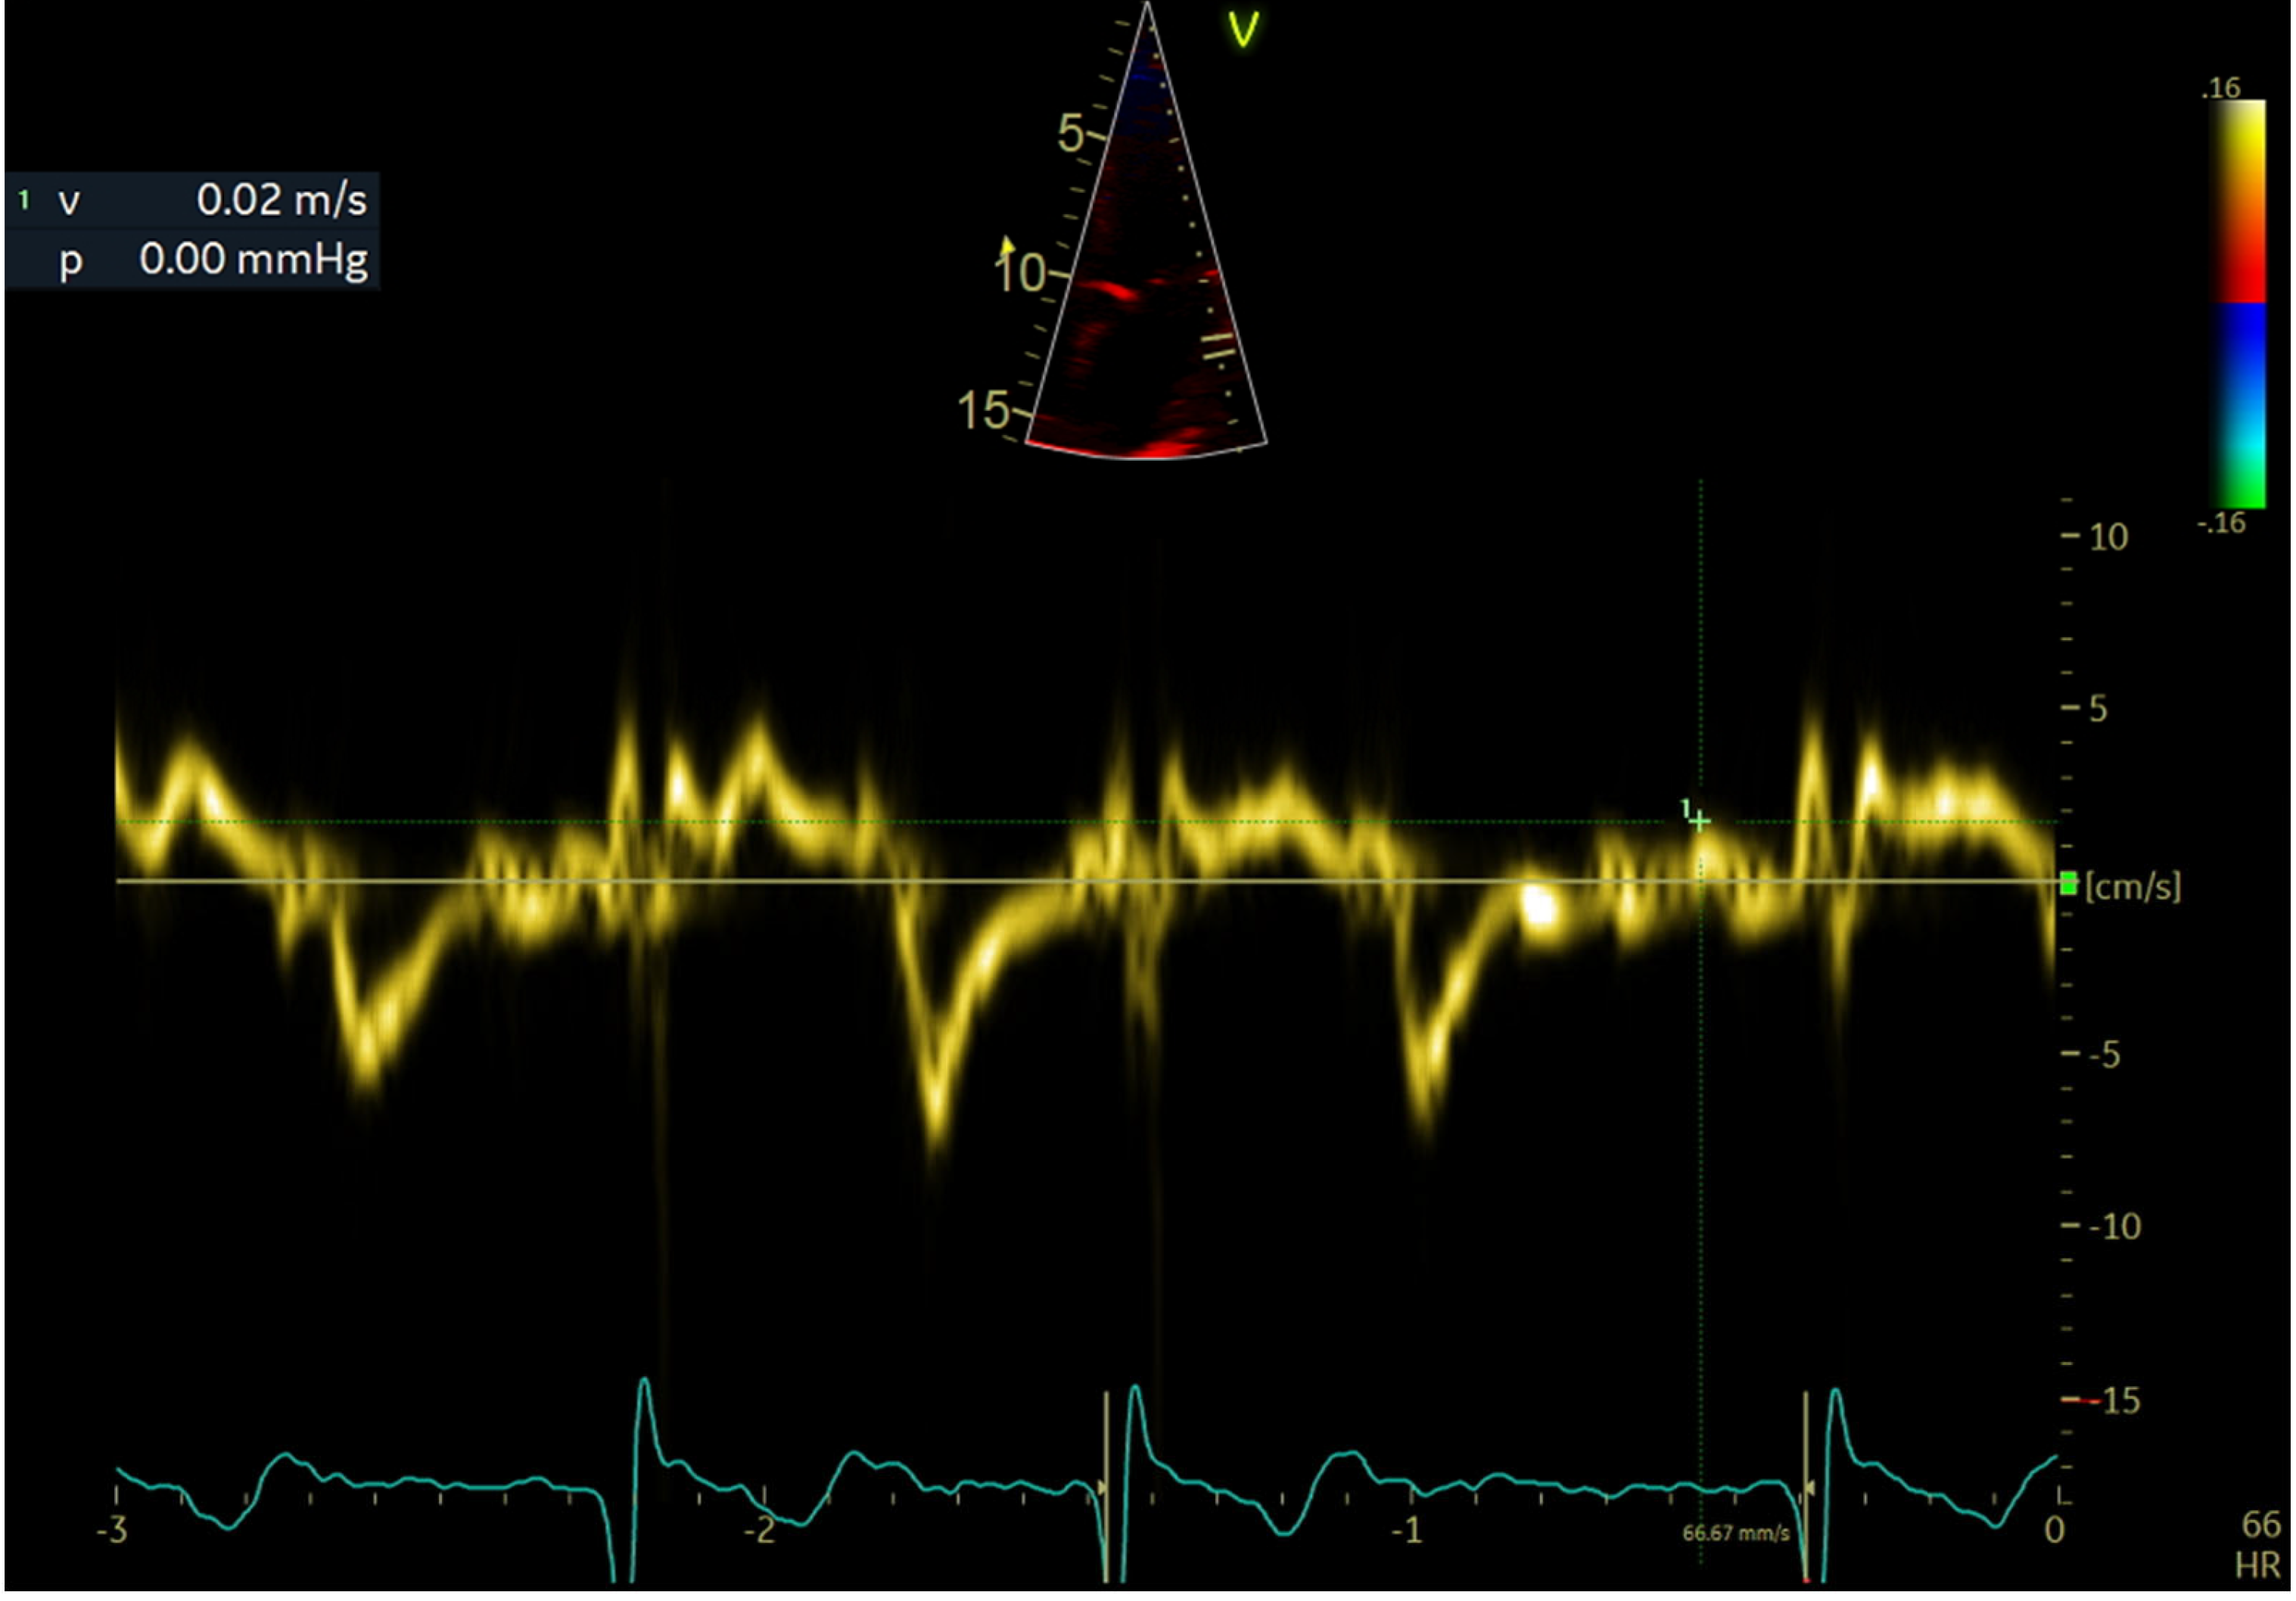

2.4. Echocardiographic Evaluation

| LAWMV (cm/s) | 3.22 (1.07) | 3.69 (0.84) | 2.86 (1.09) | <0.001 |